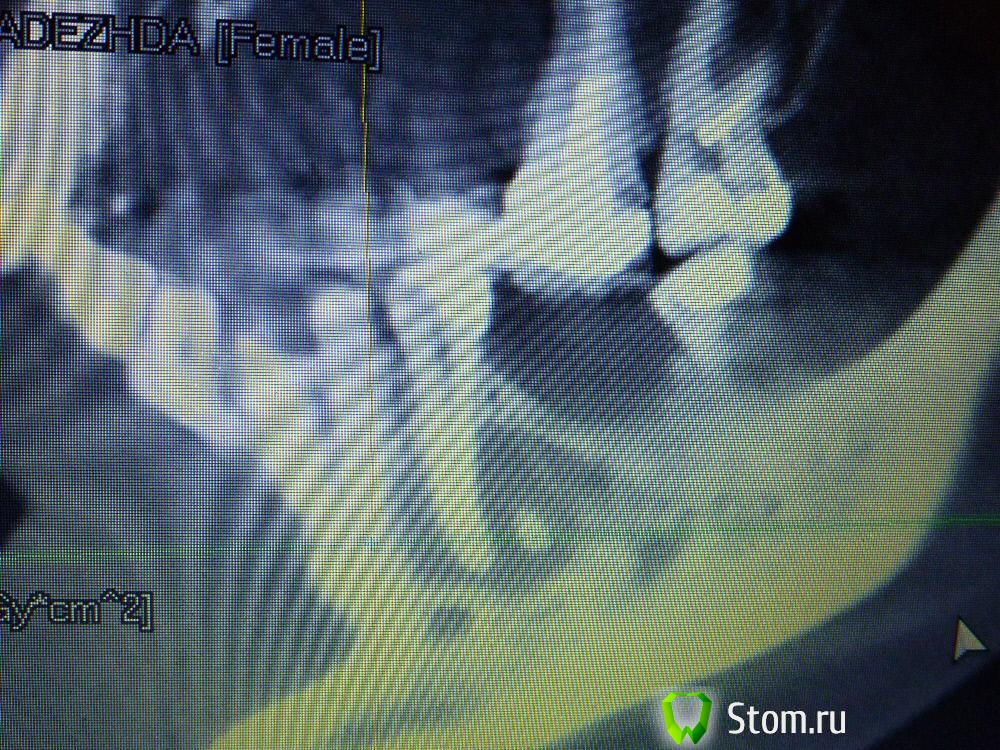

IvanK Опубликовано 25 ноября, 2011 Поделиться Опубликовано 25 ноября, 2011 Коллеги , посоветуйте Ваш план лечения.Пациентка обратилась с целью протезирования. Была направлена на ОПТГ. Обнаружены "кисты".Предположены амелобластома или первичная киста. Направлена на кафедру в 1 мед. Сказали, что "обычные кисты".Вижу 2 варианта:1). эндодонтическое лечение, цистэктомия, гистология, резекция верхушек корней, наблюдение, далее костная пластика?, имплантация. 2) Удаление зубов с периапикальными изменениями + 8-ка, гистология, пластика, имплантация боковых отделов. Ссылка на комментарий

IvanK Опубликовано 25 ноября, 2011 Автор Поделиться Опубликовано 25 ноября, 2011 Сразу прошу прощение за качество фотографий Ссылка на комментарий

koss Опубликовано 26 ноября, 2011 Поделиться Опубликовано 26 ноября, 2011 34 это полные вилы в плане эндодонтии . но попробовать было бы интересно Ссылка на комментарий

Afffinity Опубликовано 26 ноября, 2011 Поделиться Опубликовано 26 ноября, 2011 ИМХО, 38 и 45 лучше удалить Ссылка на комментарий

Corvalus Опубликовано 26 ноября, 2011 Поделиться Опубликовано 26 ноября, 2011 Эндодонтическое лечение: 45,44,33-го тоже он в зоне кисты,34,36. Хуже дела обстоят с 35-м, глянуть бы прицельный снимок, если периапикальные изменения есть, то шуруп трудно достать будет. Обязательно реэндодонтия 43. Далее цистэктомия без всяких резекций с обязательной гистологией. Заполнять кисты не стал бы, достаточно крови, очаг гнойный. Через несколько недель парадонтологическое лечение, после костная пластика с отсроченной имплантацией. И в конце рациональное протезирование одиночными коронками. При нормальном эндодонтическом лечении рецедива кист не должно быть, а если и будет, то не на всех зубах сразу. Себе зубы удалять не стал бы, опыт лечения таких зубов есть, с имплантацией всегда решить можно по ходу поступления проблем. Второй вариант имеет место быть. Объяснить пациентке все за и против, пусть сама выбирает. Ссылка на комментарий